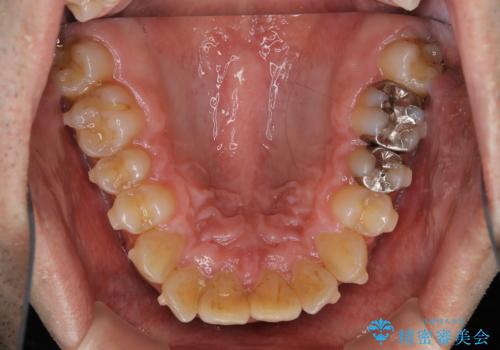

しぶといステインもエアフローワンで1日でキレイに!!

- インビザラインの治療中ですが、歯石やステインが気になるとのことでした。

コーヒーが大好きでよく飲むそうです。

全体的に歯石やステインが付着していたため、エアフロー60分コースを行いました。